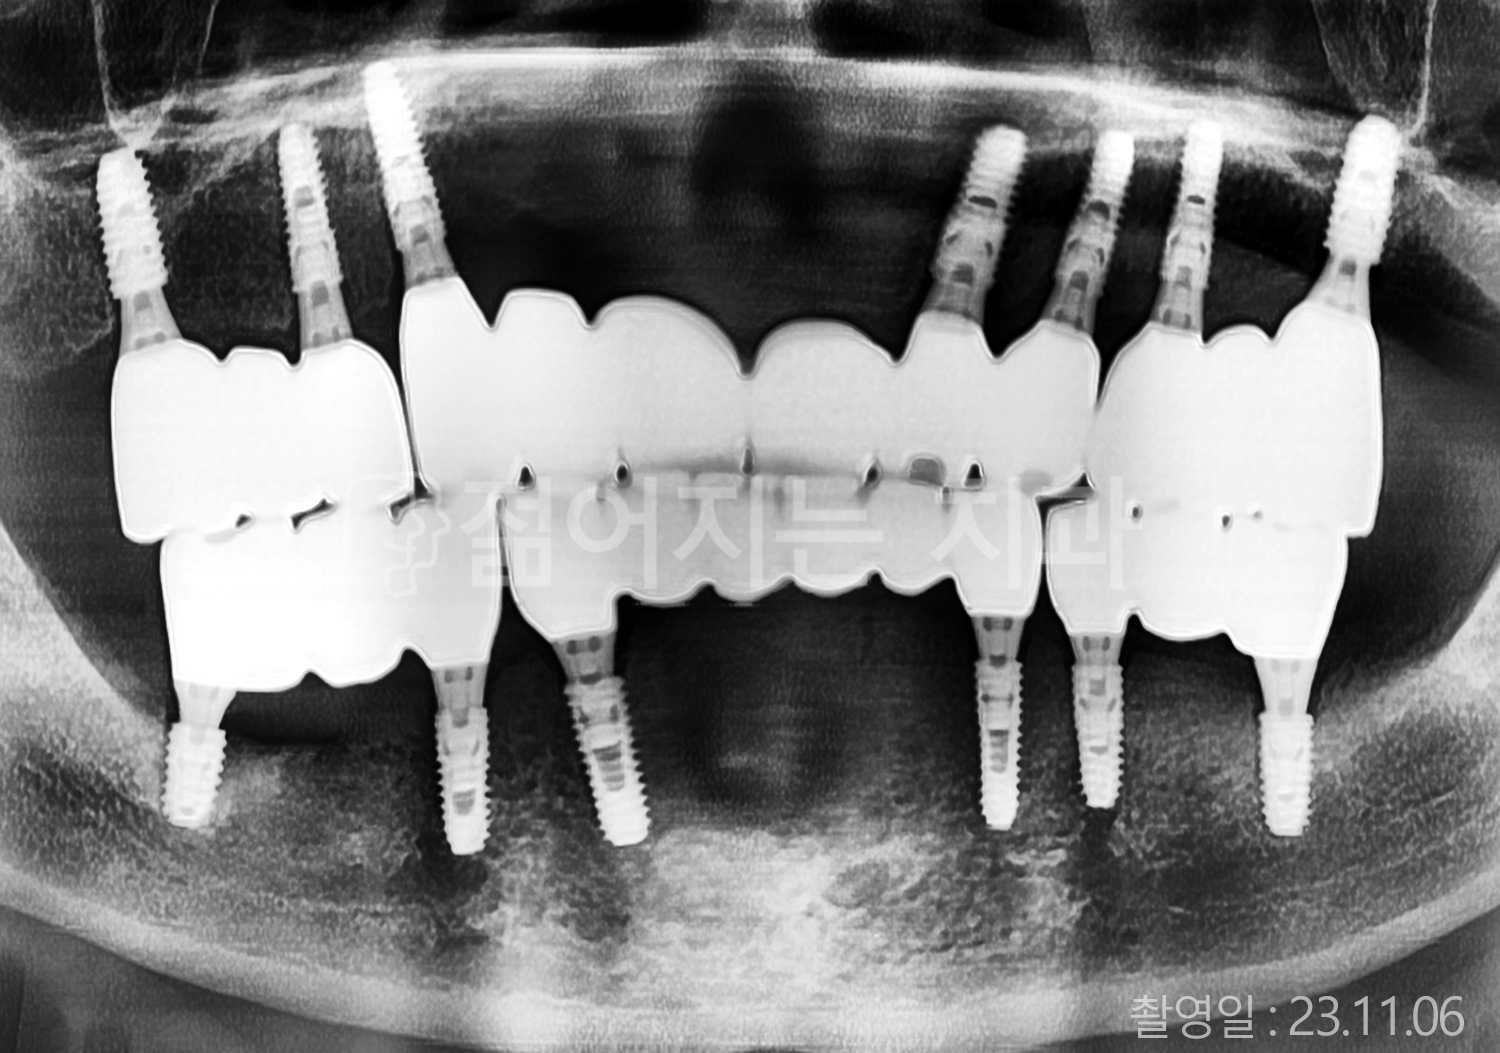

• 40대 전체치아 10개 이상 임플란트

• 60대 전체치아 10개 이상 임플란트

• 60대 고혈압, 당뇨, 고지혈증 전체치아 10개 이상 임플란트

• 50대 전체치아 10개 이상 임플란트